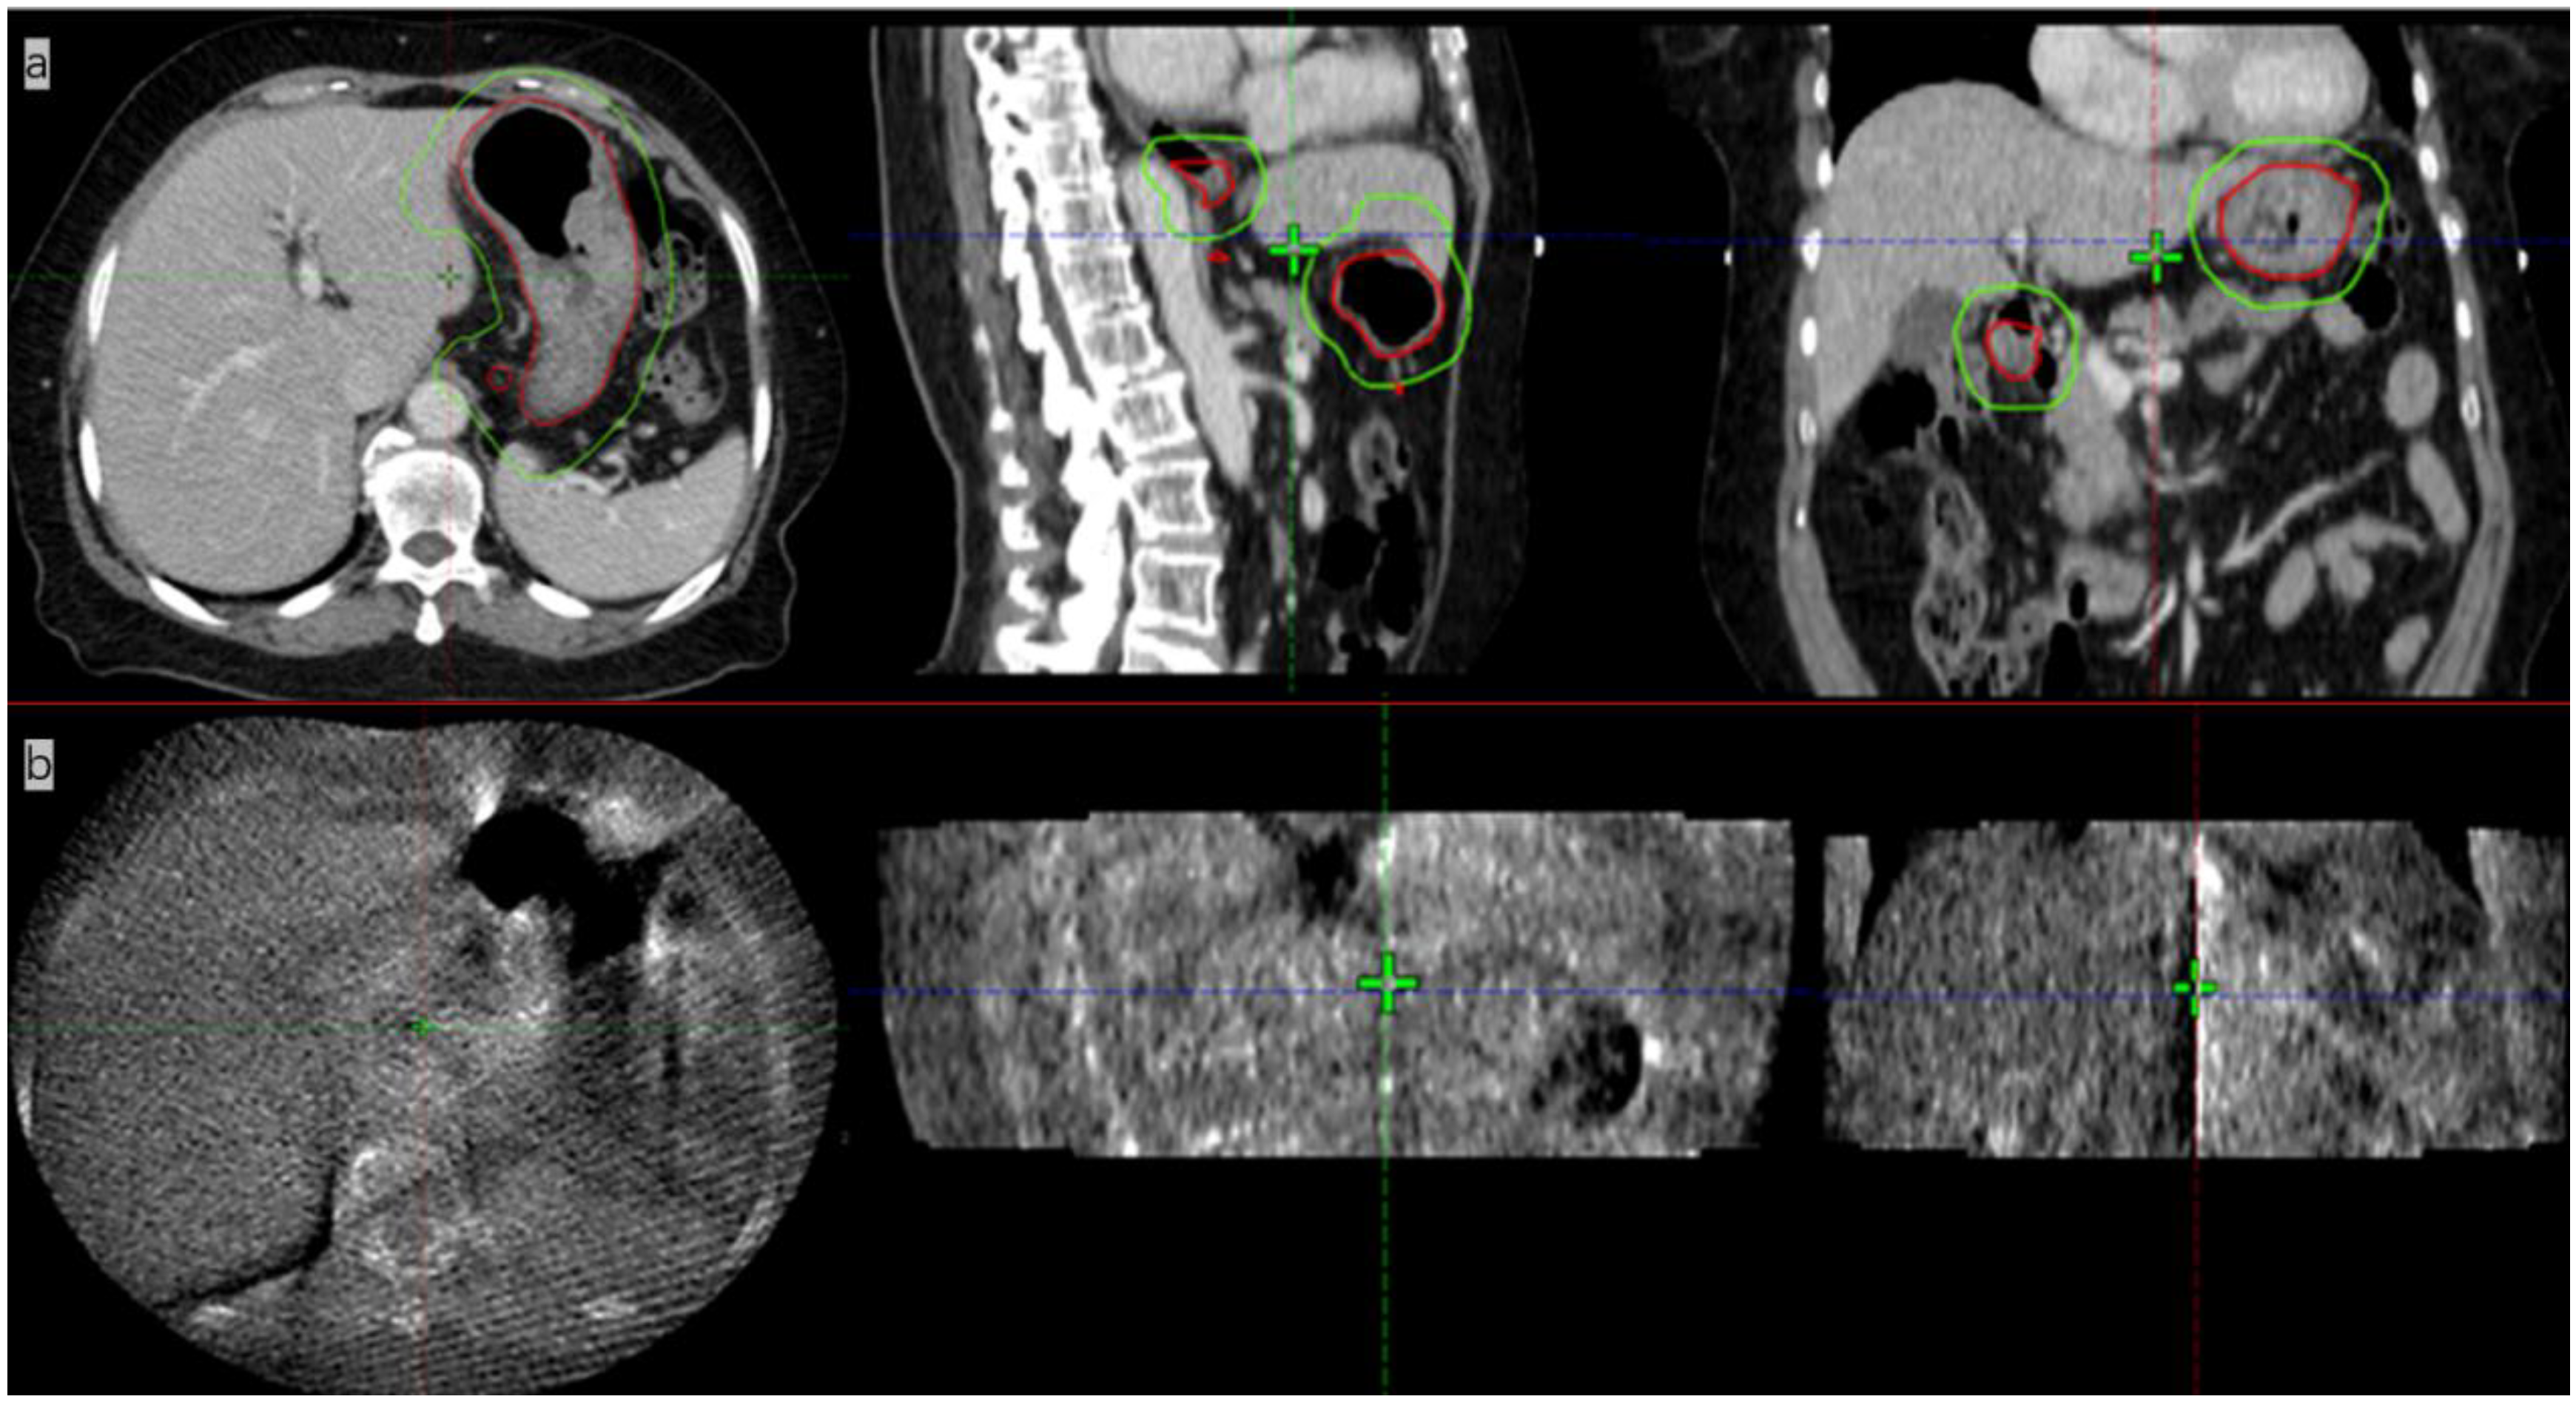

Figure 4.

Stomach delineation DSC (number in Figure) of real-time MR imaging and simulation CT imaging the (red line delineates the stomach on the simulation images, the green line delineates the stomach on the daily MRI images, and the yellow line delineates the stomach considering 1 cm external expansion from the iCTV).

We calculated the DSC after stomach delineation of real-time MR imaging and simulation CT imaging. Interestingly, we found that the patient’s inter-fractional stomach variation changed greatly. With CBCT online guidance, even after expanding the PTV by 1 cm as usual, there remain 8/15 axis planes that could not cover the entire stomach; therefore, the target, i.e., the entire stomach, would be missed (Figure 4) At the same time, we could monitor the organs around the stomach, such as liver, left kidney, and spinal cord, which were irradiated daily, and compared their state them with that of the same organs after a mean dose in the CT simulation. (Table 1) The liver and duodenum were on average less exposed to toxic doses in each MRI-guided treatment than in the CT simulation (liver: 840.7 cGy < 929.1 cGy, duodenum: 874.9 cGy < 1025.1 cGy). Although the average doses received by the spinal cord and the left kidney were slightly higher in MRI-guided therapy than in CT simulation (spinal cord:483.3 cGy > 470.8 cGy, left kidney: 297.7 cGy > 277.7 cGy), they were far lower than their respective dose constraints (the maximum dose constraint for the spinal cord is 4500 cGy, and the average kidney dose constraint is less than 1800 cGy) [8].

IGRT has become routine as a standard configuration in modern radiation therapy. Imaging the patient prior to treatment can help reduce the impact of setup errors, thus improving the dose delivery accuracy [13]. Currently, most modern radiotherapy systems are equipped with kV CBCT to visualize anatomical structures and identify the target volumes. Although CBCT is highly effective, it provides images with poor quality for soft tissues—including abdominal organs such as the liver, stomach, and pancreas—which makes it very difficult to accurately identify the soft-tissue targets and surrounding OARs. In the case of our gastric MALT lymphoma patient shown in Figure 5, it was not feasible to use CBCT for image guidance because of its poor image quality. A larger PTV margin with at least 1 cm had to be delineated, but this would cause higher toxicity to OARs. In addition, a 1 cm margin could not cover the entire empty stomach even if anisodamine (dose 10 mg) was administered to reduce gastric motility (Figure 4) [14] (pp. 174–177). As shown in Figure 4, even after expanding the PTV by 1 cm as usual with CBCT online guidance, there remain 8/15 axis planes that could not cover the entire stomach. Therefore, the target, i.e., the entire stomach, would be missed in regular clinical practice without MRI image guidance. Poor CBCT imaging of the stomach makes it more challenging to incorporate corrections for certain differences in routine patient anatomy, as well as to use approaches based on adaptive treatment protocols. The MR-LINAC system overcomes the limitations of traditional IGRT, especially for soft tissues requiring the precise definition of the target and of OARs. MR-LINAC improves IGRT by enhancing soft-tissue contrast in MR images without delivering concomitant radiation doses. MR-LINAC brings a unique emerging workflow that can help radiation therapy practitioners improve their skills and understand MR anatomy. The case reported here illustrates that MR-LINAC could visualize the stomach clearly, especially after administering anisodamine. Meanwhile, an attractive option for MR-LINAC might be to re-optimize or adjust the therapeutic plan before each radiation treatment. Diagnostic-quality MR images can be acquired based on the actual patient anatomy before and during treatment and then used in an online adaptive workflow. Compared to CBCT, online 1.5 T MRI provides better target visualization on an MR-LINAC and aids online adaptive treatment strategies, including daily replanning. Although online adaptation techniques guided by CBCT are improving, the quality of stomach images obtained by CBCT is likely to remain poor. In contrast, in MRI-guided therapy, increased soft-tissue contrast can more accurately visualize day-to-day variations and may allow the delineation of a smaller PTV margin, thus reducing OAR toxicity [15].